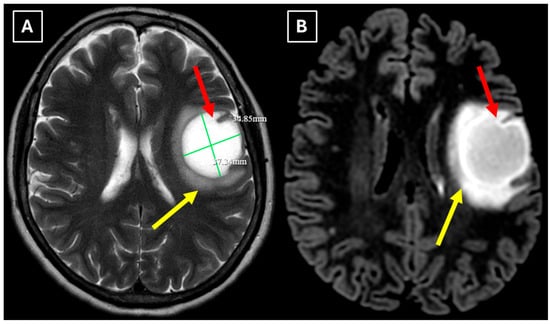

Figure 1. Native head CT without I/V contrast Images (A,B) show a. Hypodense lesion in the left hemisphere, basal parts of the frontal lobe. Measuring up to at least 3.5 cm in maximum size, with mild perifocal edema. Red arrow—indistinct formation.

One week later, a brain MRI with intravenous contrast was performed, which revealed a well-defined subcortical lesion approximately 3.5 cm in diameter in the posterior basal parts of the left frontal lobe, accompanied by perifocal edema and sulcal effacement (Figure 2). No pathological contrast enhancement was observed (Figure 3). No other white matter lesion was identified to suggest signs of leukodystrophy, and no hemosiderin deposits were identified in the brain or meninges (Figure 3). Given the T2/FLAIR mismatch (Figure 2), the most likely diagnosis was infiltrative low-grade astrocytoma. The patient received mannitol anti-edema therapy, resulting in clinical improvement and a reduction in neurological symptoms. The case was discussed by a multidisciplinary team (neurologist, neurosurgeon, radiologist, oncologist, and pathologist). Surgical treatment and morphological verification of the tumor were recommended. A day later the patient was discharged from the hospital in a stable condition, with a recommendation to be admitted to the neurosurgery department for surgery in two weeks. She was prescribed dexamethasone tablets of 0.5 mg twice daily on an outpatient basis.

Figure 2. MRI scan of the brain. (A): Axial T2-weighted sequence shows a well-defined, homogenous, hyperintense mass-like lesion in the inferior part of the left frontal lobe, with involvement of the juxtacortical white matter and relative sparing of the cortical gray matter. The lesion measured 37.34 mm × 34.85 mm (AP × LL). Additionally, there is incomplete perifocal edema surrounding the lesion, extending to the white matter and away from the cortex. (B): Axial FLAIR sequence shows the lesion with a relatively more hypointense center and a hyperintense peripheral rim at the lesion margins. A T2/FLAIR mismatch sign was observed, making the likely diagnosis an infiltrative low-grade astrocytoma. All MRI images were acquired with the Philips “Ingenia Ambition X” 1.5T system. Red arrow—indistinct formation, yellow arrow—perifocal vasogenic edema.

Figure 3. MRI scan of the brain. (A): Axial trace image of diffusion-weighted imaging (DWI) shows slight diffusion restriction in the lesion wall when correlated with (B): dark signal on apparent diffusion coefficient (ADC) maps in the wall of the lesion, with no central diffusion reduction observed. (C): In the corresponding axial slice of the susceptibility-weighted imaging (SWI) sequence, there is no evidence of blood products within the lesion. (D): On the axial postcontrast T1-weighted imaging, there is no contrast enhancement in the lesion, although a central vein-like structure is observed. Red arrow—diffusion restriction, yellow arrow—perifocal vasogenic edema, green arrow—central vein sign.

In this case, despite the presence of a T2/FLAIR mismatch sign (Figure 2), several imaging characteristics were more suggestive of a TDL rather than IDH-mutant astrocytoma. The lesion was located in juxtacortical white matter and had cortical sparing, which is unusual for IDH-mutant astrocytomas, since they typically have been shown to infiltrate and expand the cortex. The diffusion restriction at the lesion margin with centrally elevated ADC values was more consistent with reported DWI findings of TDLs and contrasted with the central restriction often seen in gliomas. The mass effect was mild in comparison to the overall lesion size, favoring demyelination rather than neoplasm in this case. Additionally, the lesion had a central vein sign, as described above, a radiological sign supportive of inflammatory demyelination. The combination of cortical sparing, peripheral diffusion restriction, mild mass effect, and the appearance of central vein sign represented strong features that raised suspicion of a tumefactive demyelination lesion.